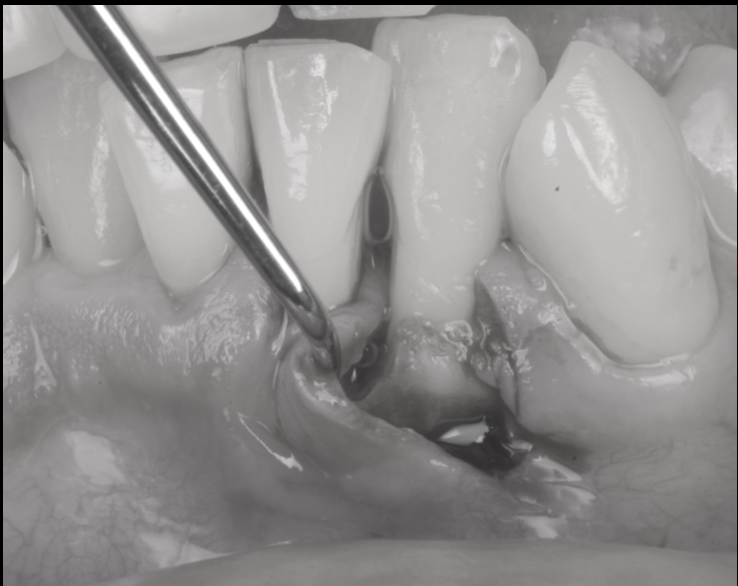

局所麻酔を行い、腫れている部分の歯ぐきをそっと開きます。

すると、歯の根の周りに深い骨のくぼみと、炎症でドロドロになった組織が確認できました。

マイクロスコープ下で、

歯石や感染したセメント・プラークを徹底的に除去し、

炎症組織を丁寧に取り除きます。